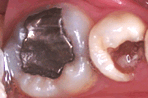

아말감으로 치료후 부서지고 충치가 재발된 모습

아말감을 이용하는 방법은 비용이 적게 드는 장점이 있으나 부위가 작은 경우를 제외하고는 잘 부서져 나가는 성질이 있습니다.

따라서 치료한 부위에서 다시 충치가 잘 생기게 됩니다.